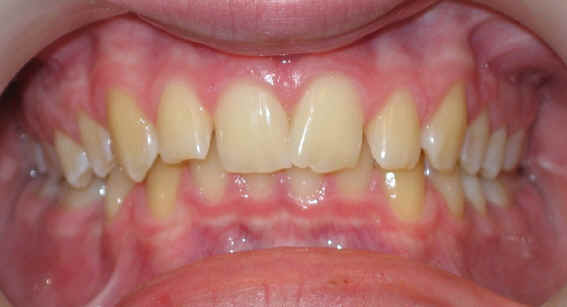

2009/12/19 U .016x.022, L .016 x .022 Niti